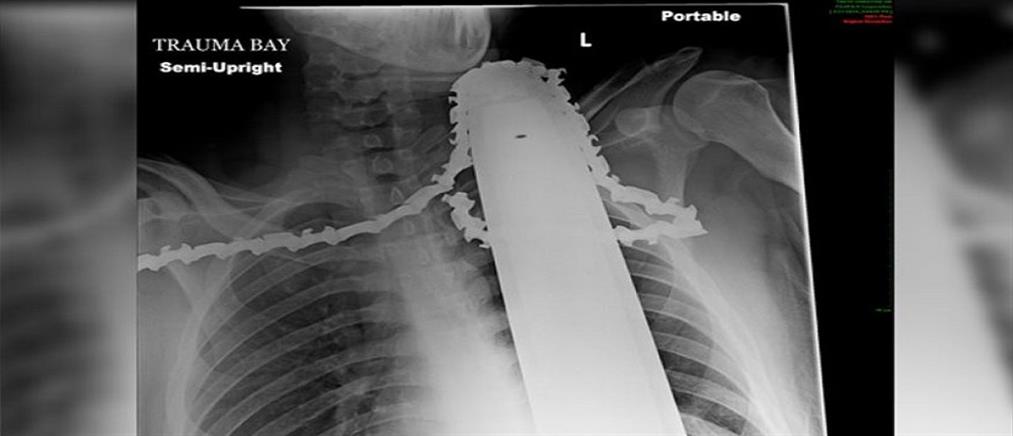

Χαλκιδική: 79χρονος καταπλακώθηκε από κορμό δέντρου στην προσπάθεια του να κόψει ξύλα

Ο άτυχος άνδρας δε φαίνεται να ήταν επαγγελματίας υλοτόμος, αλλά να επιχείρησε να κόψει ξύλα για προσωπική χρήση.